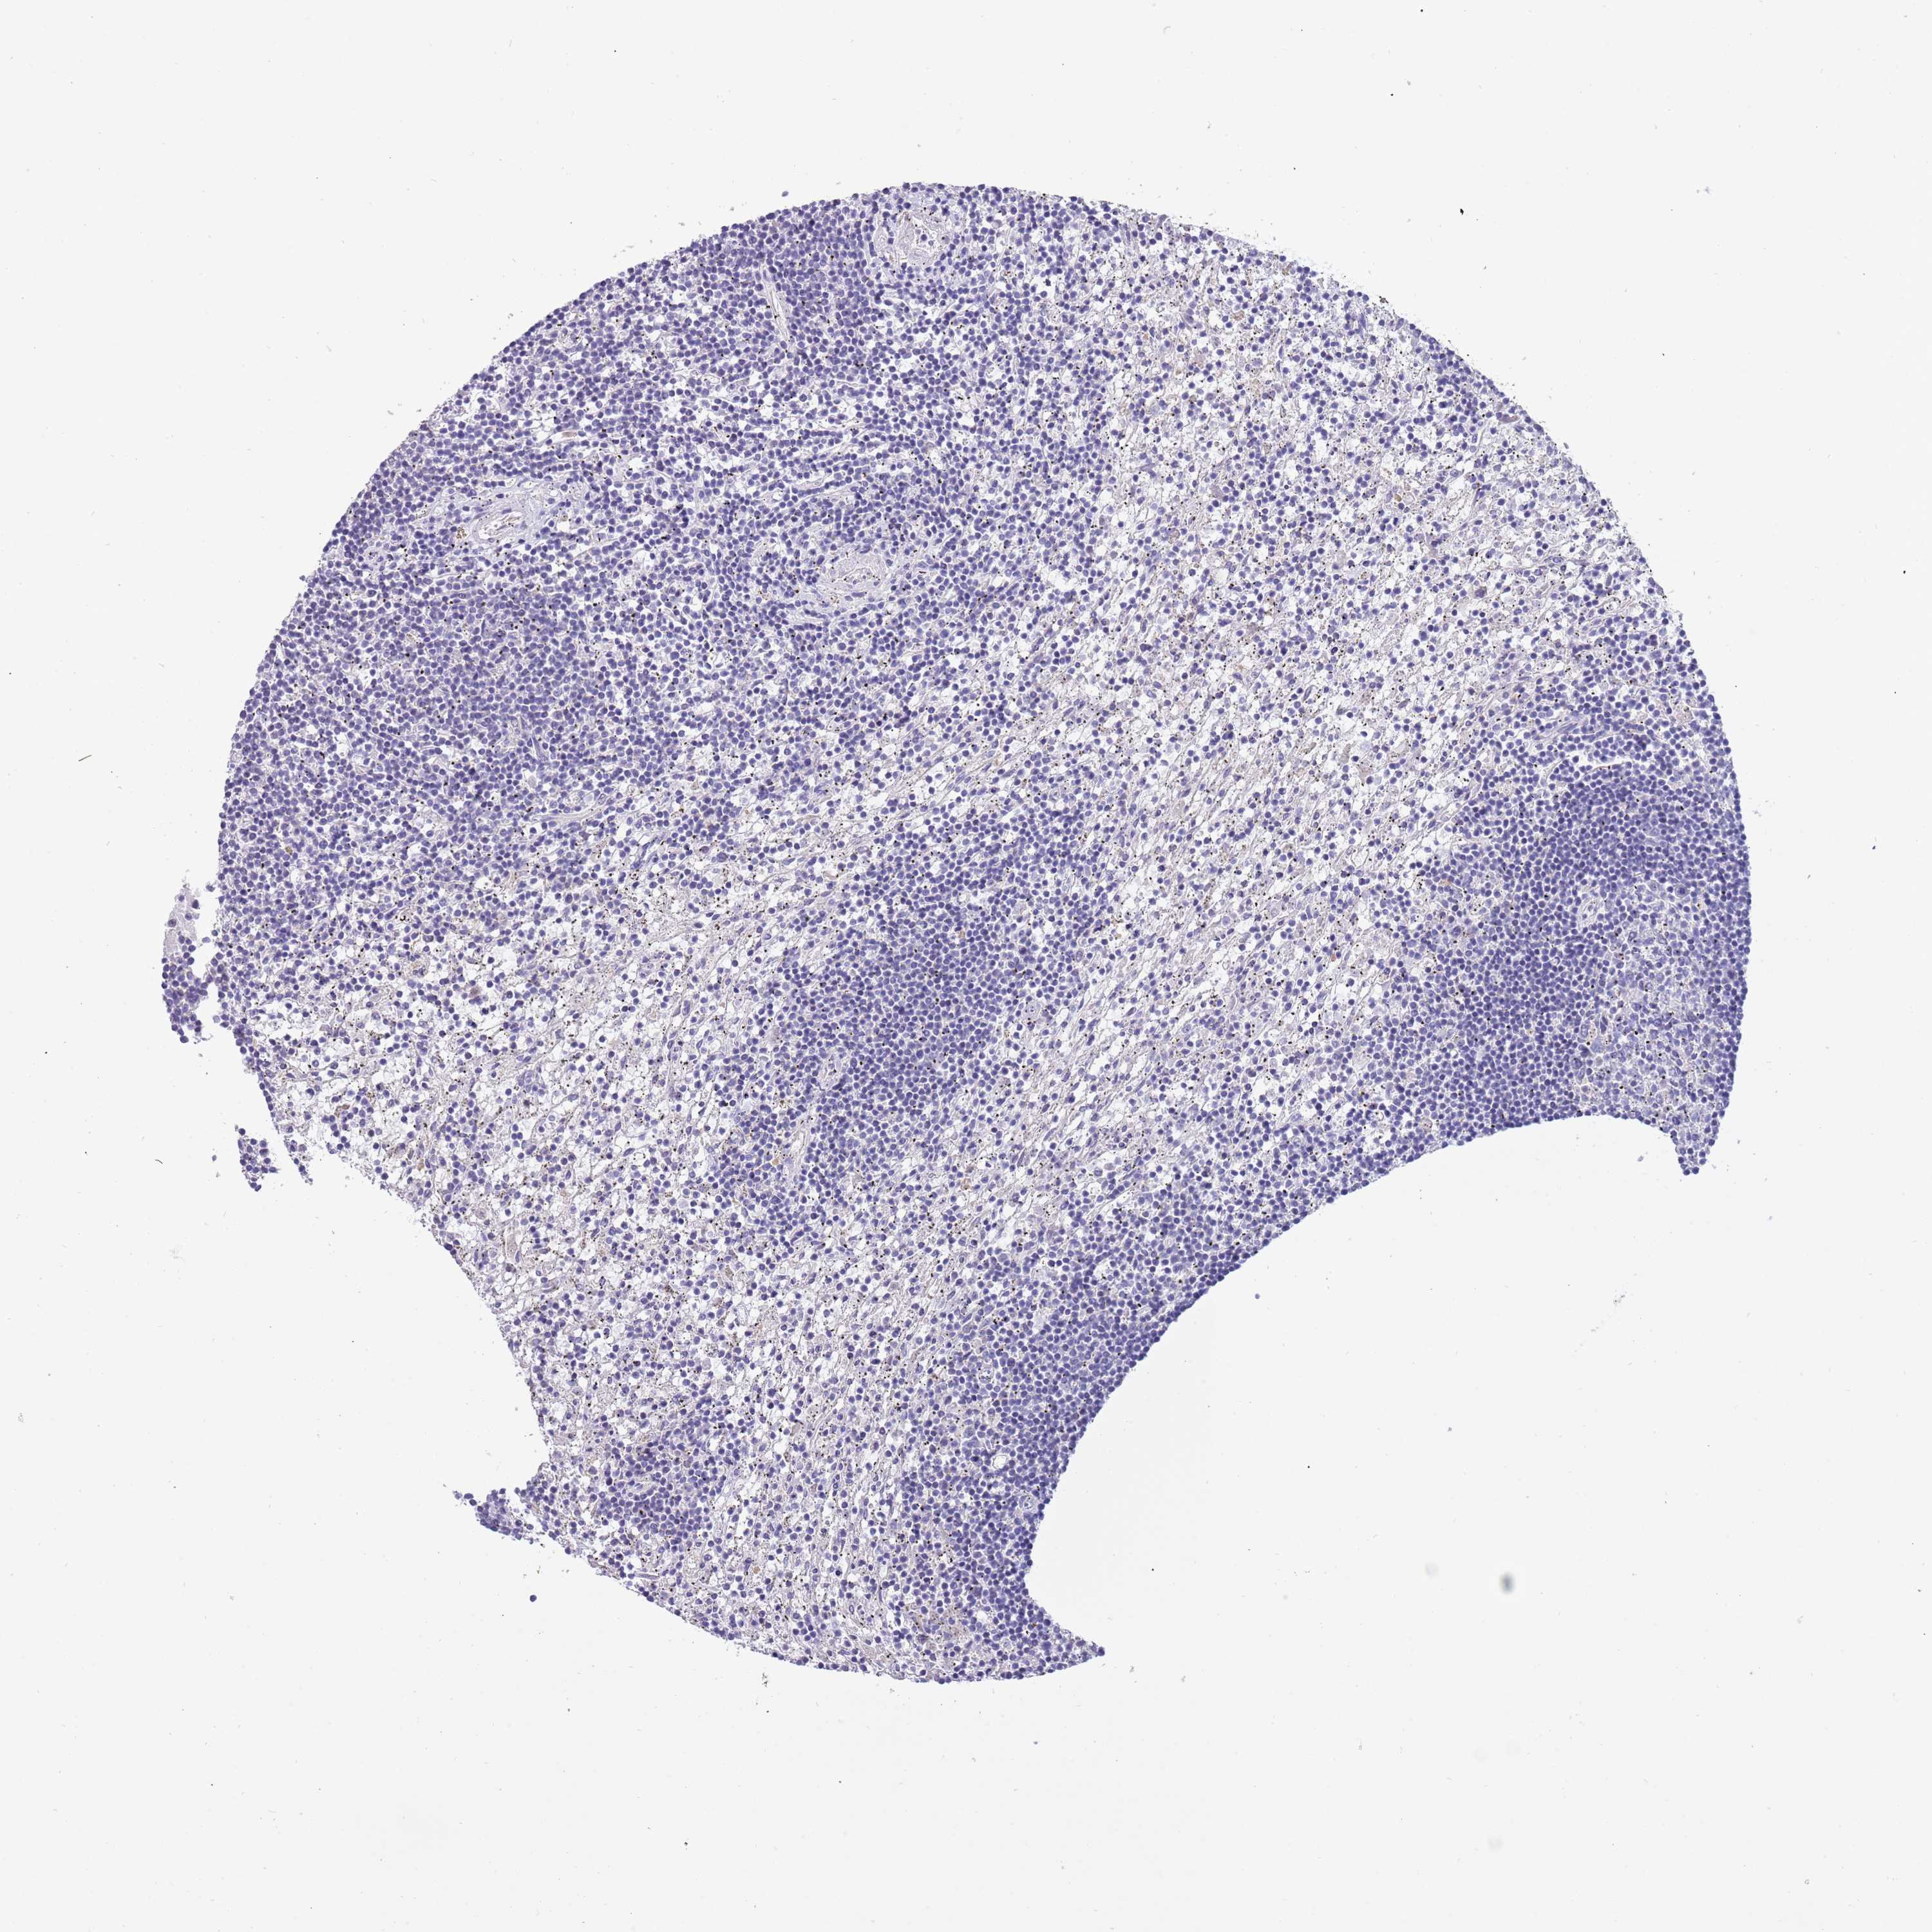

CANCER LYMPHOMA Show tissue menu

LYMPHOMA - Protein expressioni

A mouse-over function shows sample information and annotation data. Click on an image to view it in a full screen mode. Samples can be filtered based on level of antibody staining by selecting one or several of the following categories: high, medium, low and not detected. The assay and annotation is described here.

Each image is clickable and will lead to virtual microscopy that enables deeper exploration of all samples and also displays staining intensity scores, fraction scores and subcellular localization as well as patient and tissue information for each sample.

Antibody HPA047801

Hodgkin's disease, NOS

Malignant lymphoma, non-Hodgkin's type, High grade

Malignant lymphoma, non-Hodgkin's type, Low grade